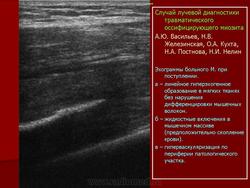

Оссифицирующий миозит

Оссифицирующий миозит